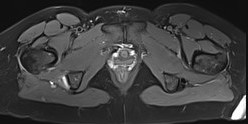

MRI

Proximal hamstring tear on right (red circle), normal insertion on tuberosity on left (blue circle)